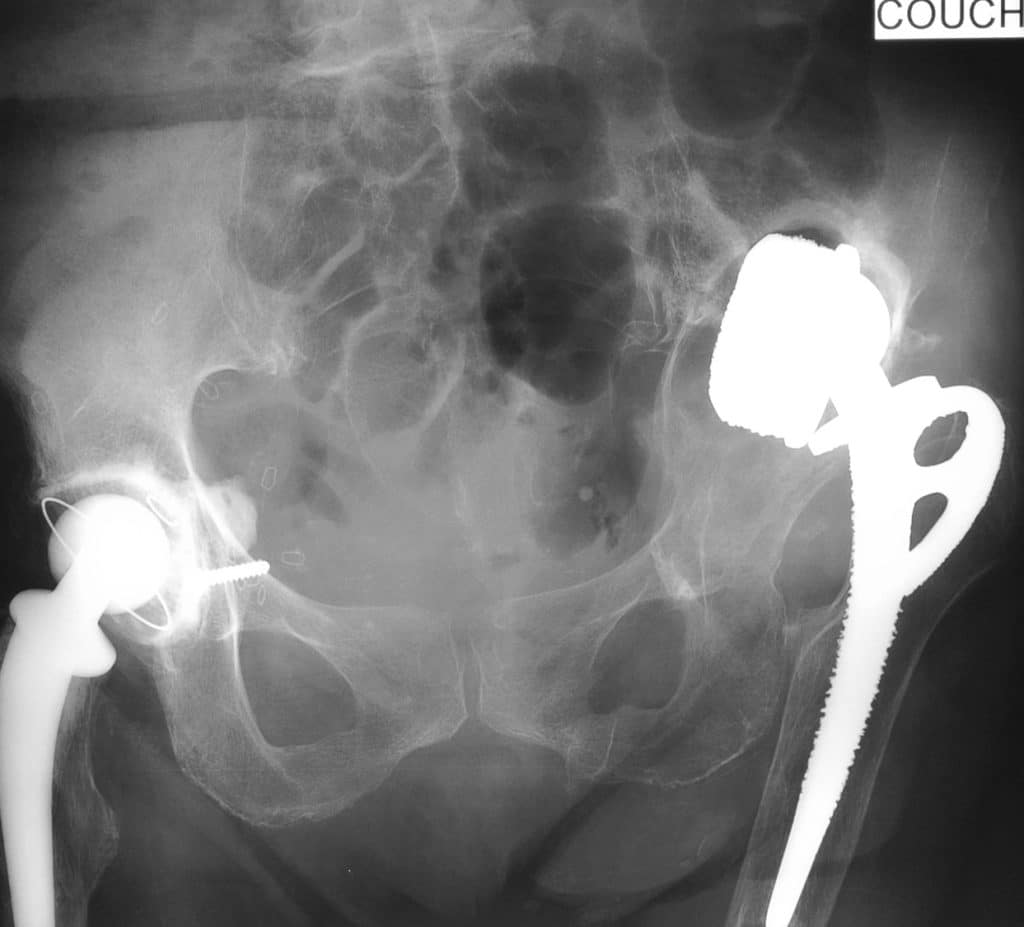

La décision de révision bipolaire a été décidée après 5 ans de surveillance, par l’apparition d’une importante tuméfaction des parties molles de la hanche et la perte brutale de la fonction articulaire.

Cette révision était considérée comme une chirurgie particulièrement difficile : fragilité de la patiente, dégâts osseux, ablation de l’ implant fémoral, corticales fémorales fantomatiques …)

Notez que le plot d’ancrage iliaque du cotyle cimenté est exactement situé au point d’introduction du plot iliaque du cotyle INTEGRA™.